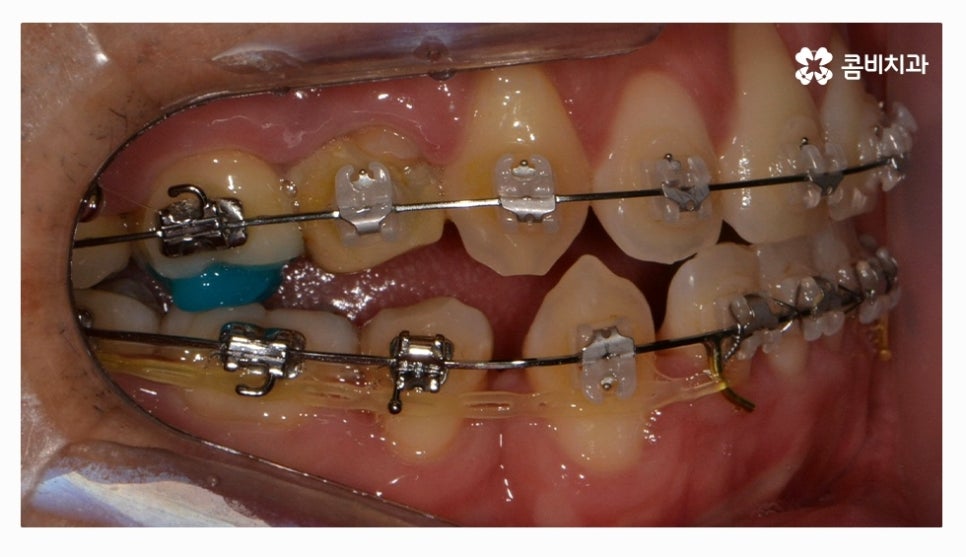

오늘 소개드릴 환자분은 윗니와 아랫니가 제대로 맞물리지 않는

부정교합 사례이며 클리피씨교정을 통해서 치료가 진행된 사례라고 할 수 있어요.

부정교합 환자분들의 경우 발치나 수술이 필요한 경우가 있는데

치아교정을 진행할 때 치아의 이동 공간을 고려해야 하므로

치간 삭제나 어금니 후방 이동으로도 치아 이동 공간이 부족하다면

발치를 필수적으로 해야 하는 경우가 있어요.

전체교정을 하시는 분들의 경우 보편적으로 많이 선택하시는

교정 장치는 클리피씨교정이라고 할 수 있을 정도로 선호도가 높으며

클리피씨교정은 자가 결찰 장치로 통증 감소 및 교정 기간을

단축시킬 수 있으며 관리가 편리하다는 장점도 갖고 있어요

클리피씨교정은 세라믹 재질이기 때문에 심미적으로도 우수한 편이며

브라켓과 와이어 고정을 위한 철사를 사용하지 않기 때문에 철사로 인해 찔리거나

입안이 뜯겨 피가 나는 경우를 예방할 수 있는데요.

클리피씨교정은 철사를 쓰지 않고 특수 클립이 내장되어

클립을 이용하여 와이어를 고정하고 열고 닫을 수 있기 때문에

교정 장치로 인한 불편함이 줄어들 수 있으며 철사를 사용하지

않는 것만으로도 보다 편안함을 느낄 수 있지만 치아를 적은 힘으로

지속적으로 이동시켜서 상대적으로 통증이 적고 치과 내원 횟수도 줄일 수 있어요.

위 환자는 총 치료기간 약 30개월이 소요되었으며

개인에 따라 치료 기간 및 결과가 차이가 있을 수 있고,

개인에 따라 출혈 및 부작용이 발생할 수 있습니다.